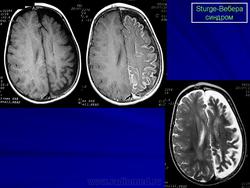

Магнитная резонансная томография пациента с болезнью Штурге - Вебера

Магнитная резонансная томография пациента с болезнью Штурге - Вебера